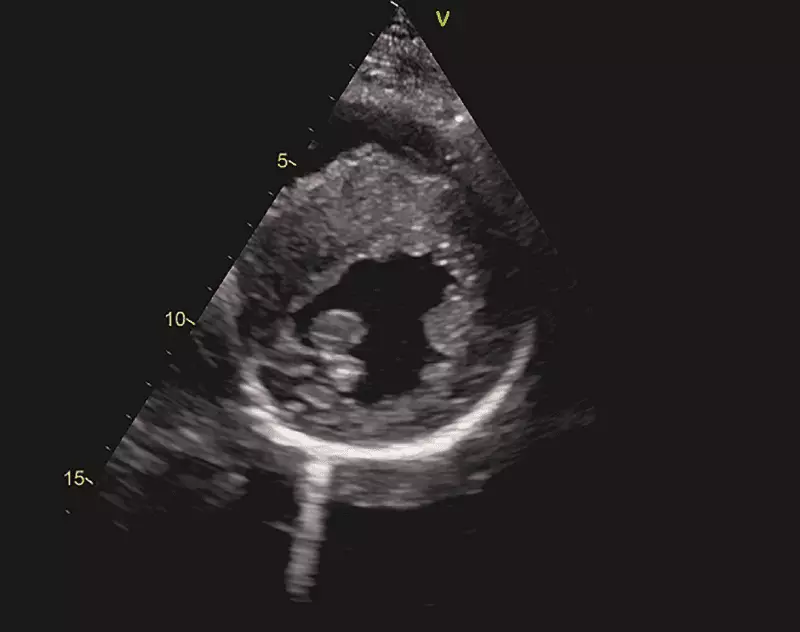

Odrębną, a jednocześnie najrzadszą grupę pacjentów z omdleniami kardiogennymi, stanowią pacjenci z chorobami organicznymi serca, które są przyczyną zaburzeń hemodynamicznych prowadzących do zmniejszenia przepływu mózgowego lub są substratem do istotnych zaburzeń rytmu serca. Zaliczamy do nich wady zastawkowe, np. zwężenie zastawki aortalnej, wypadanie zastawki mitralnej, dysfunkcje protez zastawkowych, złożone wady serca zarówno przed leczeniem operacyjnym, np. tetralogia Fallota, jak i po korekcji operacyjnej, wrodzone anomalie tętnic wieńcowych, kardiomiopatię rozstrzeniową, przerostową zawężającą i niezawężającą, arytmogenną dysplazję prawej komory, zapalenie mięśnia sercowego (ryc. 6).

W tej grupie pacjentów podstawowym badaniem diagnostycznym jest echokardiografia [18]. Tylko ocena anatomiczna, ocena przepływów w jamach serca i dużych naczyniach z użyciem funkcji Dopplera oraz pomiary jam serca pozwalają na postawienie rozpoznania nieprawidłowości strukturalnych i funkcjonalnych mięśnia sercowego. W szczególnych sytuacjach, gdy wykonane badania są niewystarczające na postawienie ostatecznego rozpoznania, sięgamy po dodatkowe metody badawcze. I tak w podejrzeniu ostrego rozwarstwienia aorty czy zatoru tętnicy płucnej metodą z wyboru pozostaje tomografia komputerowa z użyciem kontrastu. W przypadku podejrzenia masy patologicznej w obrębie jam serca, miokardium czy osierdzia, najlepszym wyborem pozostaje rezonans magnetyczny serca. W przypadku echokardiograficznego podejrzenia nadciśnienia płucnego jedynym weryfikującym badaniem pozostaje cewnikowanie serca.

Ryc. 6. Badanie echokardiograficzne dziewczynki 13-letniej z zasłabnięciami w czasie wysiłku w wywiadzie. Projekcja naczyniowa długa (a) i naczyniowa krótka (b) – widoczny istotny przerost przegrody międzykomorowej do około 31 mm (norma według BSA –10 mm). Na podstawie badania echokardiograficznego rozpoznano kardiomiopatię przerostową